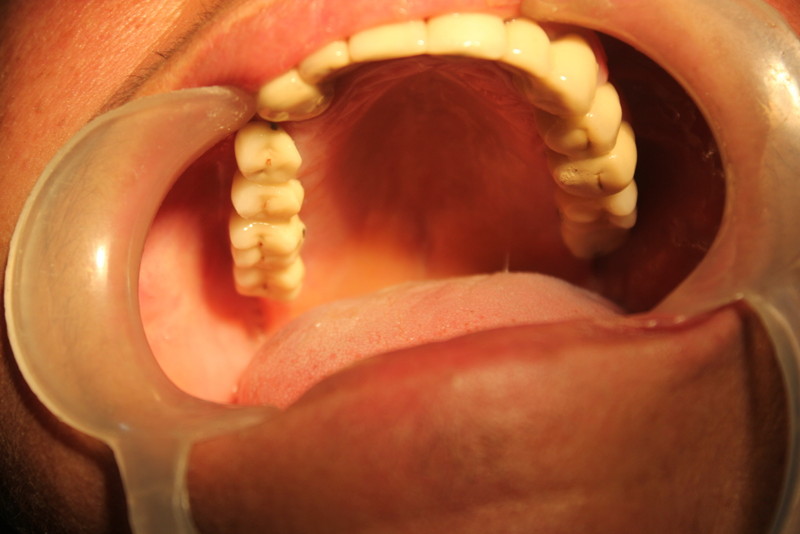

Complete Oral Rehabilitation